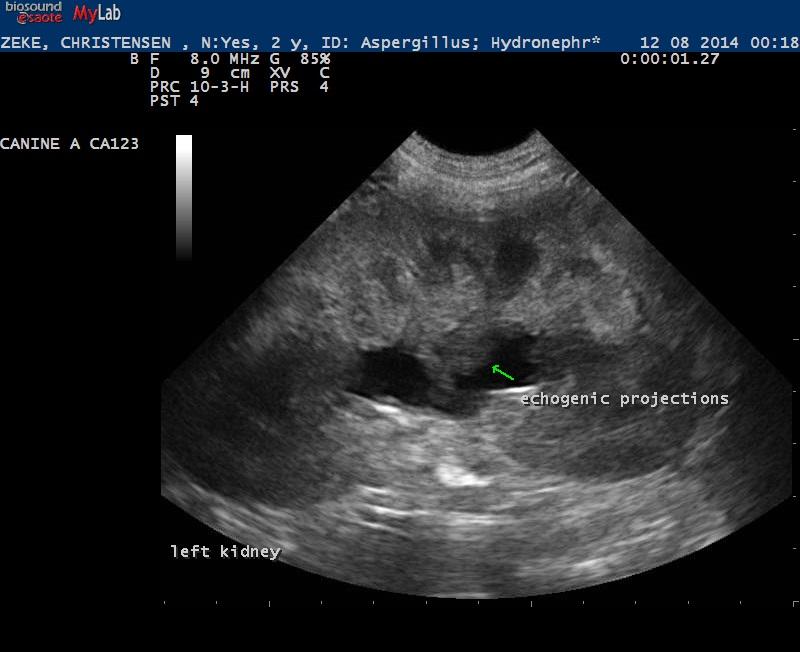

A 2-year-old MN German Shepherd was presented for anorexia, lethargy, exhibiting acute renal failure and the following labs: Azotemia (BUN >130; Creat 9.9), USG=1.012, Hyperblilrubinemia, and Leukocytosis (52,000).